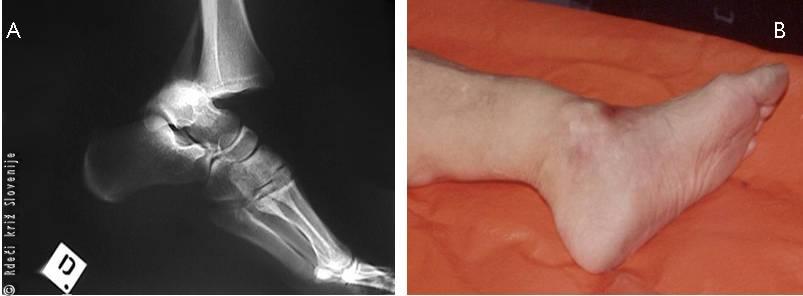

Slika 8

Rentgenska (A) in klinična (B) slika prikazuje izpah skočnega sklepa.